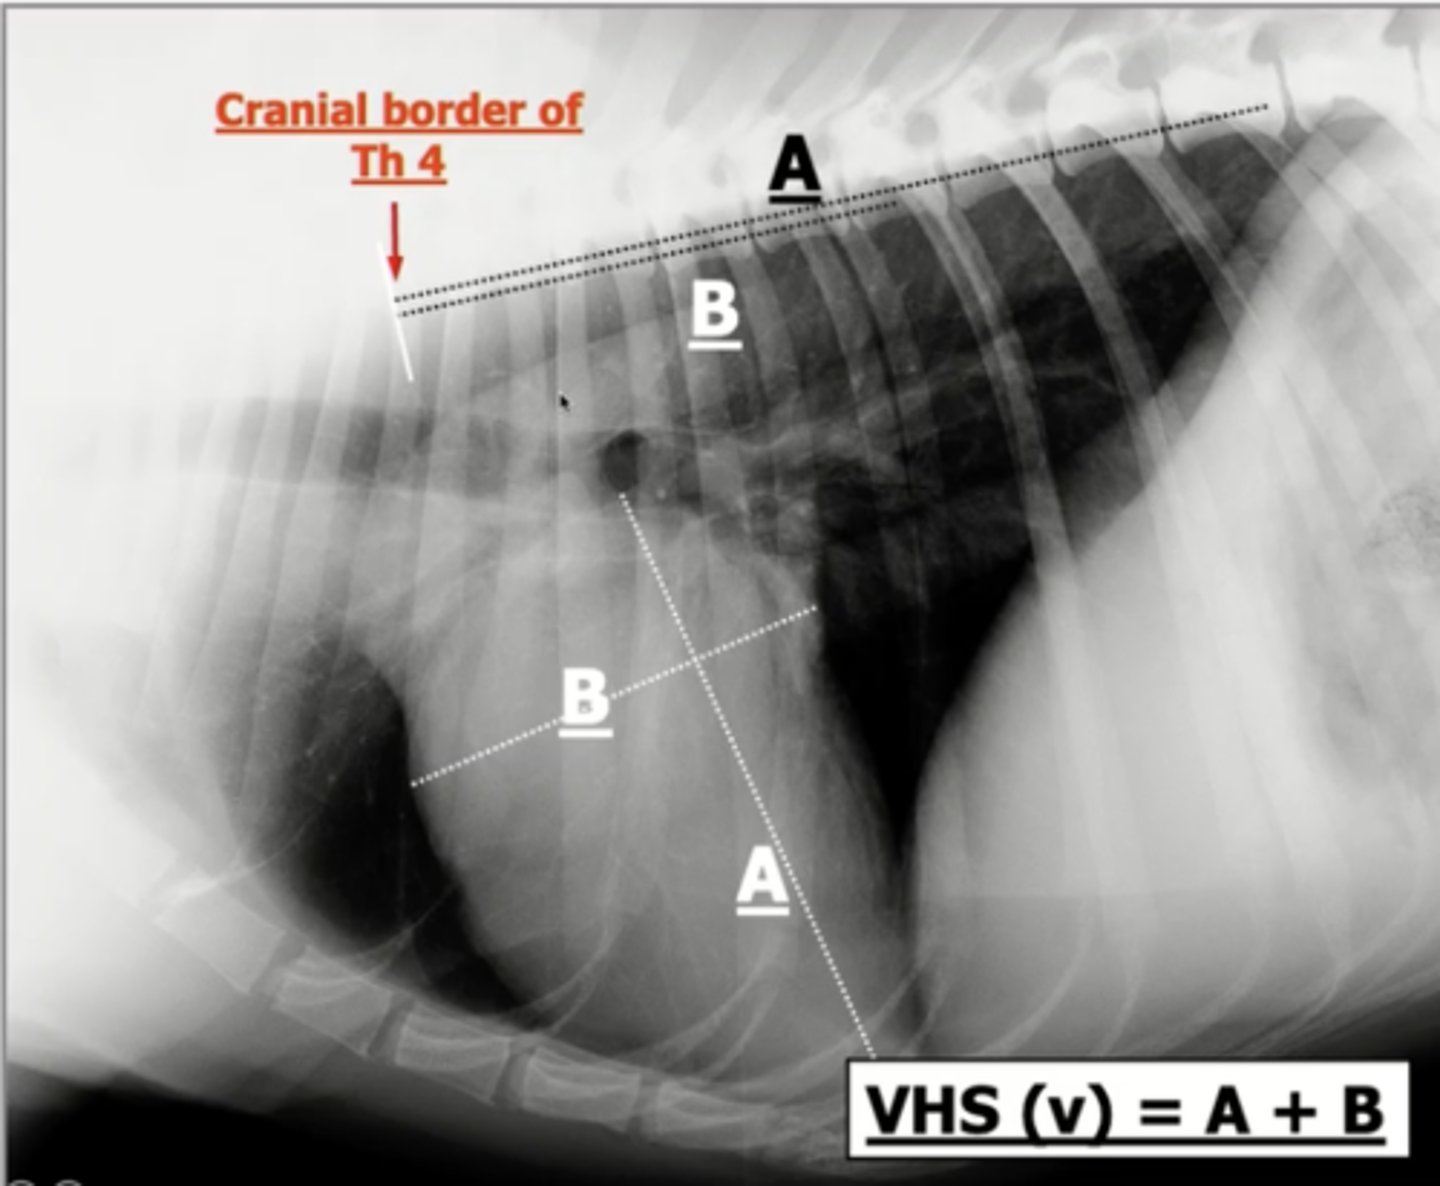

How is the vertebral heart scale (VHS) determined? (5)

1.) measure the long axis of the heart

2.) measure the short axis of the heart (width)

3.) interpose both measurements onto the vertebrae, starting at T4

4.) count each of the vertebrae that span over both measurements

5.) add the number of vertebrae for the long and short axis together

What position are animals in to measure the vertebral heart scale (VHS)?

lateral recumbency